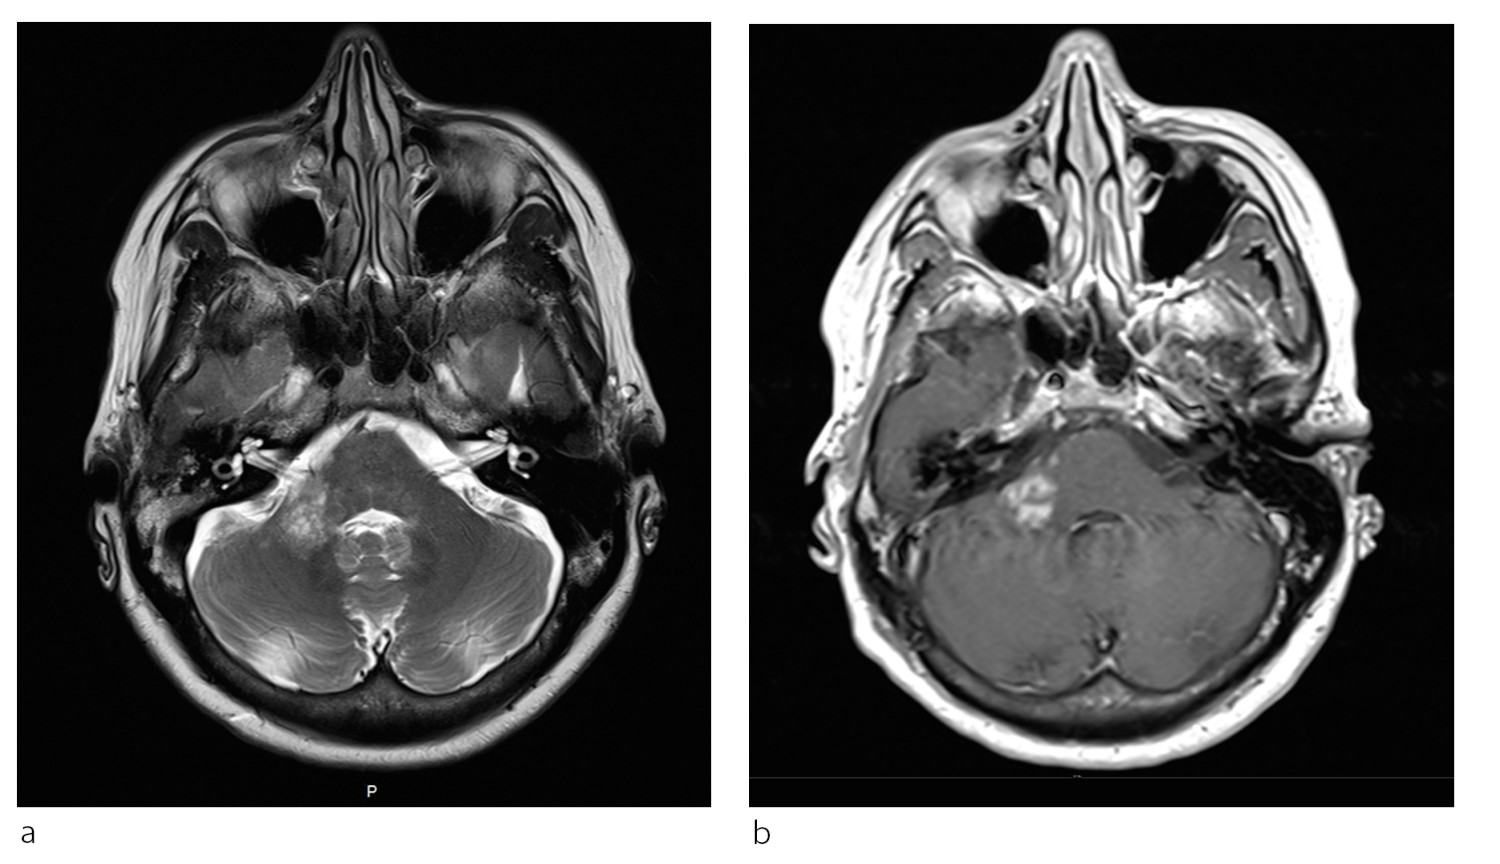

Ved mistanke om progredierende multifokal leukoencafalopati skal det gjennomføres MR-undersøkelse. Forandringer kan ses i hjernens hvite substans som multiple små lesjoner og/eller større konfluerende områder hvor som helst i storehjernen, oftest subkortikalt (fig 1), og i lillehjerne og hjernestamme (fig 3). Signalforandringer i ryggmargen bør gi mistanke om annen lidelse, men kan angivelig forekomme ved progredierende multifokal leukoencafalopati, men svært sjelden (20). Normale MR-bilder utelukker vanligvis tilstanden, men ved vedvarende klinisk mistanke bør undersøkelsen gjentas.

Dersom det er kontrastopptak i en lesjon ved progredierende multifokal leukoencafalopati, indikerer det sterkt at det foreligger immunrekonstitusjonsinflammasjonssyndrom (IRIS) (fig 2). Dette ses relativt ofte ved både natalizumab- og hivassosiert infeksjon. En halvmåneformet cerebellær lesjon ses nesten utelukkende ved progredierende multifokal leukoencafalopati (fig 3) (20). De viktigste differensialdiagnosene inkluderer multippel sklerose, hivencefalitt eller eventuelt andre encefalitter (herpes simplex-virus, cytomegalovirus), gliomatosis cerebri, lymfom i sentralnervesystemet, akutt disseminert encefalomyelitt (ADEM), vaskulitter/cerebrale infarkter og mitokondriecytopatier (20).